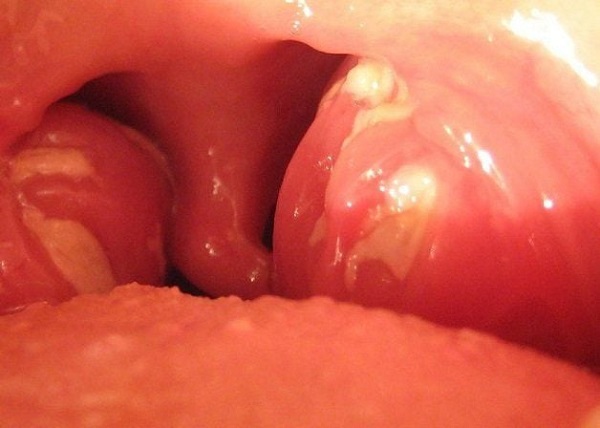

- Amidan sưng đỏ, có mảng trắng, đôi khi chảy mủ

Áp-xe quanh amidan: Biến chứng nguy hiểm không thể chủ quan

Cơ chế bệnh lý chủ yếu là do ổ viêm “ăn sâu”, mủ không thoát ra được, tích tụ quanh amidan, gây sưng đau dữ dội, phù nề, thậm chí biến dạng vùng cổ họng, khó há miệng, khó nuốt, sốt cao liên tục, mệt mỏi kéo dài.